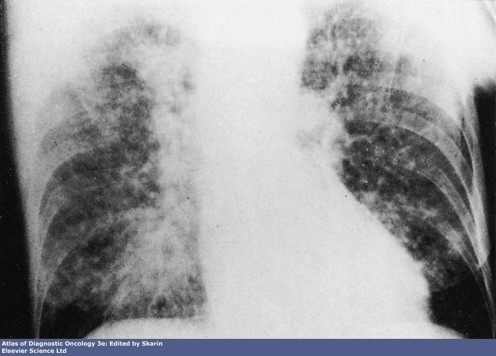

CXR: